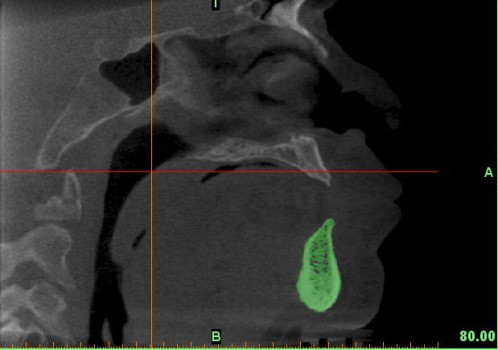

En caso de que el médico cirujano o institución solicitante posea alguna capacidad de impresión 3D, nosotros ofrecemos el servicio de generación de los archivos en formato STL (stereolithography) necesarios para imprimir una pieza ósea en una impresora 3D.

En caso de que el médico cirujano o institución solicitante posea alguna capacidad de impresión 3D, nosotros podemos ofrecer el servicio de generación de los archivos con formato STL (stereolithography) necesarios para imprimir una pieza ósea en una impresora 3D. Los archivos STL también son usados para generar modelos computacionales de las piezas óseas tanto para visualización como para simulación computacional.